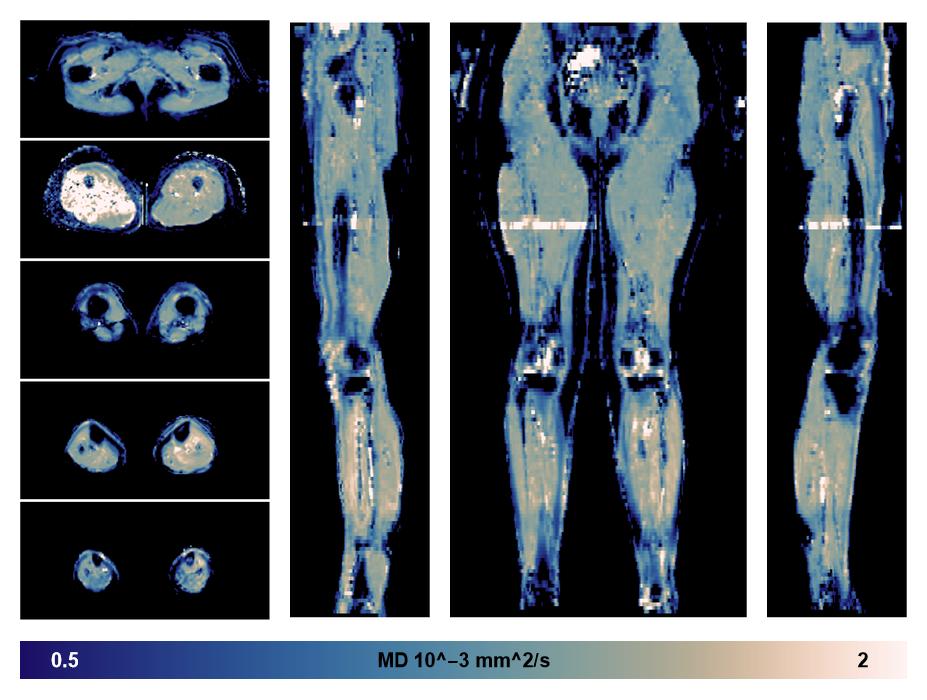

• Mean diffusivity

IVIM corrected whole leg muscle mean diffusivity obtained from diffusion tensor imaging.